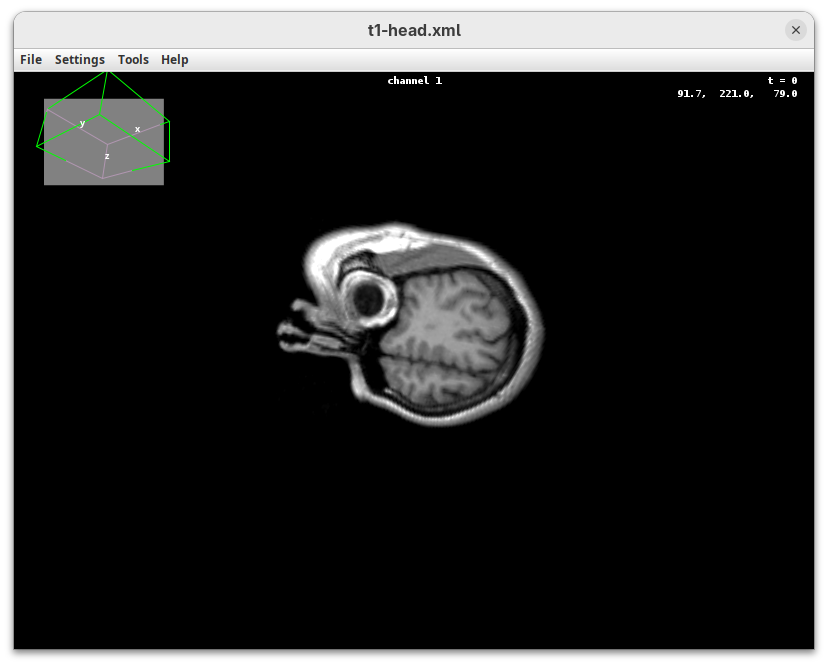

The transformation menu has controls for rotating, translating, and scaling the sample. We can either add values or manually interact with the 3D Animation window to reorient the sample. Let’s try the latter.

- Left-click on the head and move it around.

That’s a great way to see your sample from different angles. And note that the values in the Transformation panel get updated every time you move the sample interactively. In this way you can roughly position the sample and then check and update the precise values for the target transformation.

- Press

Resetand change theRotation Yto180to look at the right side of the head.